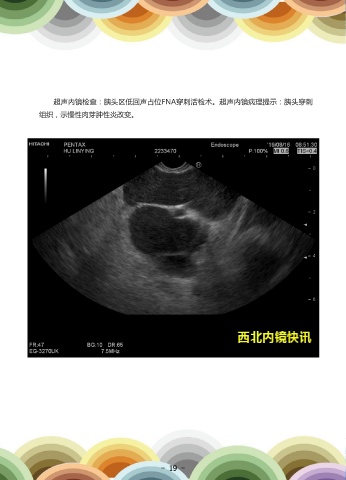

患者女,78岁,因“左下腹阵发性疼痛2月”就诊。胰腺平扫+增强CT示:1.胰尾                                        超声内镜检查:胰头区低回声占位FNA穿刺活检术。超声内镜病理提示:胰头穿刺

部占位性病变,粘液性囊腺癌可能。2.胰头上方异常强化团块影。                                                  组织,示慢性肉芽肿性炎改变。